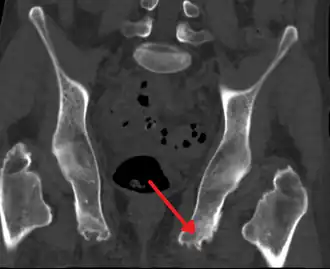

Enthésopathie du bassin probablement due à une spondylarthrite ankylosante